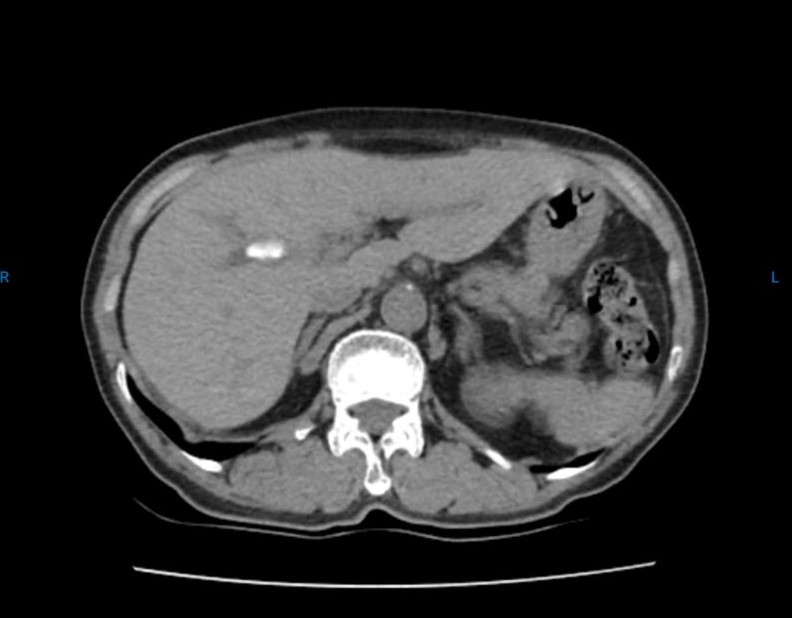

Bn nữ 44 tuổi đau thượng vị nhiều đợt. Đi khám và được chẩn đoán xơ teo thùy gan trái do sỏi gan trái. Sau hội chẩn được chỉ định cắt thùy gan trái nội soi. Trong ca mổ chung tôi đã sử dụng dao hàn mạch Ligasure và Stapler để tiến hành cắt gan trái cho bệnh nhân. Ca mổ đã diễn ra thuận lợi không chảy máu. BN ra viện sau 7 ngày.

Hình ảnh sỏi và phần gan được cắt bỏ qua nội soi.